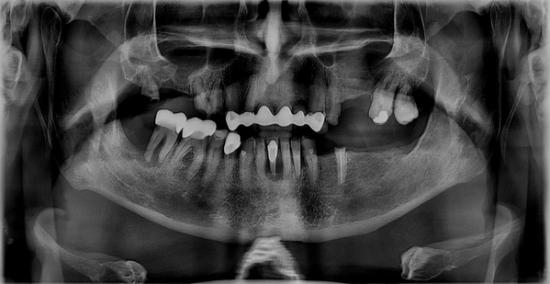

Before Photo